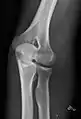

- آرنج - AP و جانبی. تصاویر موجود سر استخوان رادیوس در صورت درخواست.

پروجکشن جانبی

پروجکشن قدامی خلفی

پروجکشن مایل داخلی ۳۰ درجه آرنج چپ

پروجکشن مایل خارجی ۳۰ درجه آرنج چپ